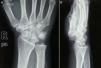

99mTc-Methylene diphosphonate (MDP) triple phase bone scintigraphy (BS) has a role in early diagnosis of Kienbock's disease, especially when the X-ray is negative. Early diagnosis can result in prompt management of the patient since wrist pain in older individuals due to aging may go unnoticed or be due to other diagnoses with the production of greater damage and eventually a worse prognosis. Herein, we present a case report of a 29-year-old female with Kienbock's disease in whom the X-ray was negative and MRI incorrect. The 99mTc-MDP SPECT/CT BS helped the diagnosis of the disease in an early stage (stage 1) and had a clinical impact on the patient's management.